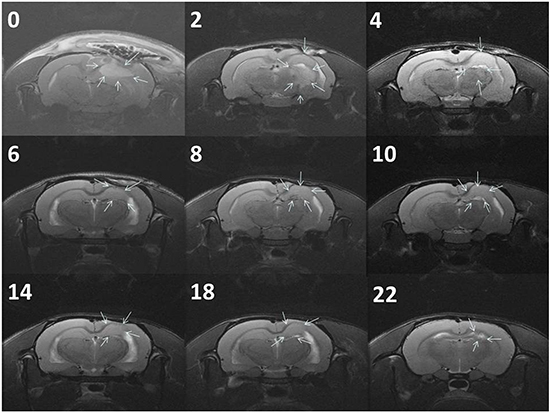

Figure 5a presents the serial MRI scans of the animals in the control group. The implanted tumour rapidly grew and resulted in an intense mass effect (midline shift and brain stem compression), eventually causing the rats to die. Figure 5b illustrates the serial brain MRI scans of the animals in the BIC group, in which the created tumour grew more slowly than in the animals in the control group. The tumour volumes decreased between Weeks 4 and 8 and thereafter progressively regrew and caused the death of the rats in Week 23. Figure 6 presents the serial brain MRI scans of the rats in the BIC group. The initial tumour volume (62.73 × 10−3 mL) was similar to the mean tumour volume in the control group (60.36 ± 38.69 × 10−3 mL). The tumour slowly grew and reached the maximum value in Week 4 and thereafter decreased steadily and nearly disappeared at the end of the study.

Figure 6: Serial MRI images of the BICC group. The rats exhibited a complete response to BICC/PLGA nanofibrous membrane treatment. The number in the upper right corner of each image indicates the number of weeks after the implantation of BICC/PLGA nanofibrous membranes. The tumour volumes clearly decreased with time, and no tumour regrowth was observed.